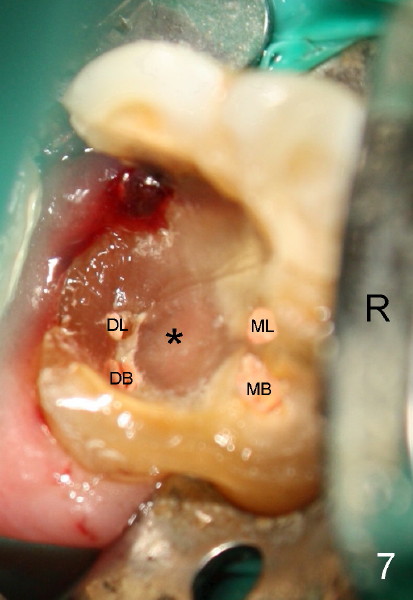

A healthy 43-year-old lady requests saving the tooth #30 with large DO caries and perioapical radiolucency (Fig.1). The tooth appears to have mesial (M) and distal (D) roots. Different angulation PA (Fig.2) and Bitewing (Fig.3) show that there are totally 4 roots/canals, which is not noted by the operator before RCT or after initiation of RCT (Fig.4). The distal canal orifice is not in the center. The distolingual (DL) canal orifice is searched without success. MB, ML, and D canals are debrided with rotary file 30/.04 at working lengths (WL).